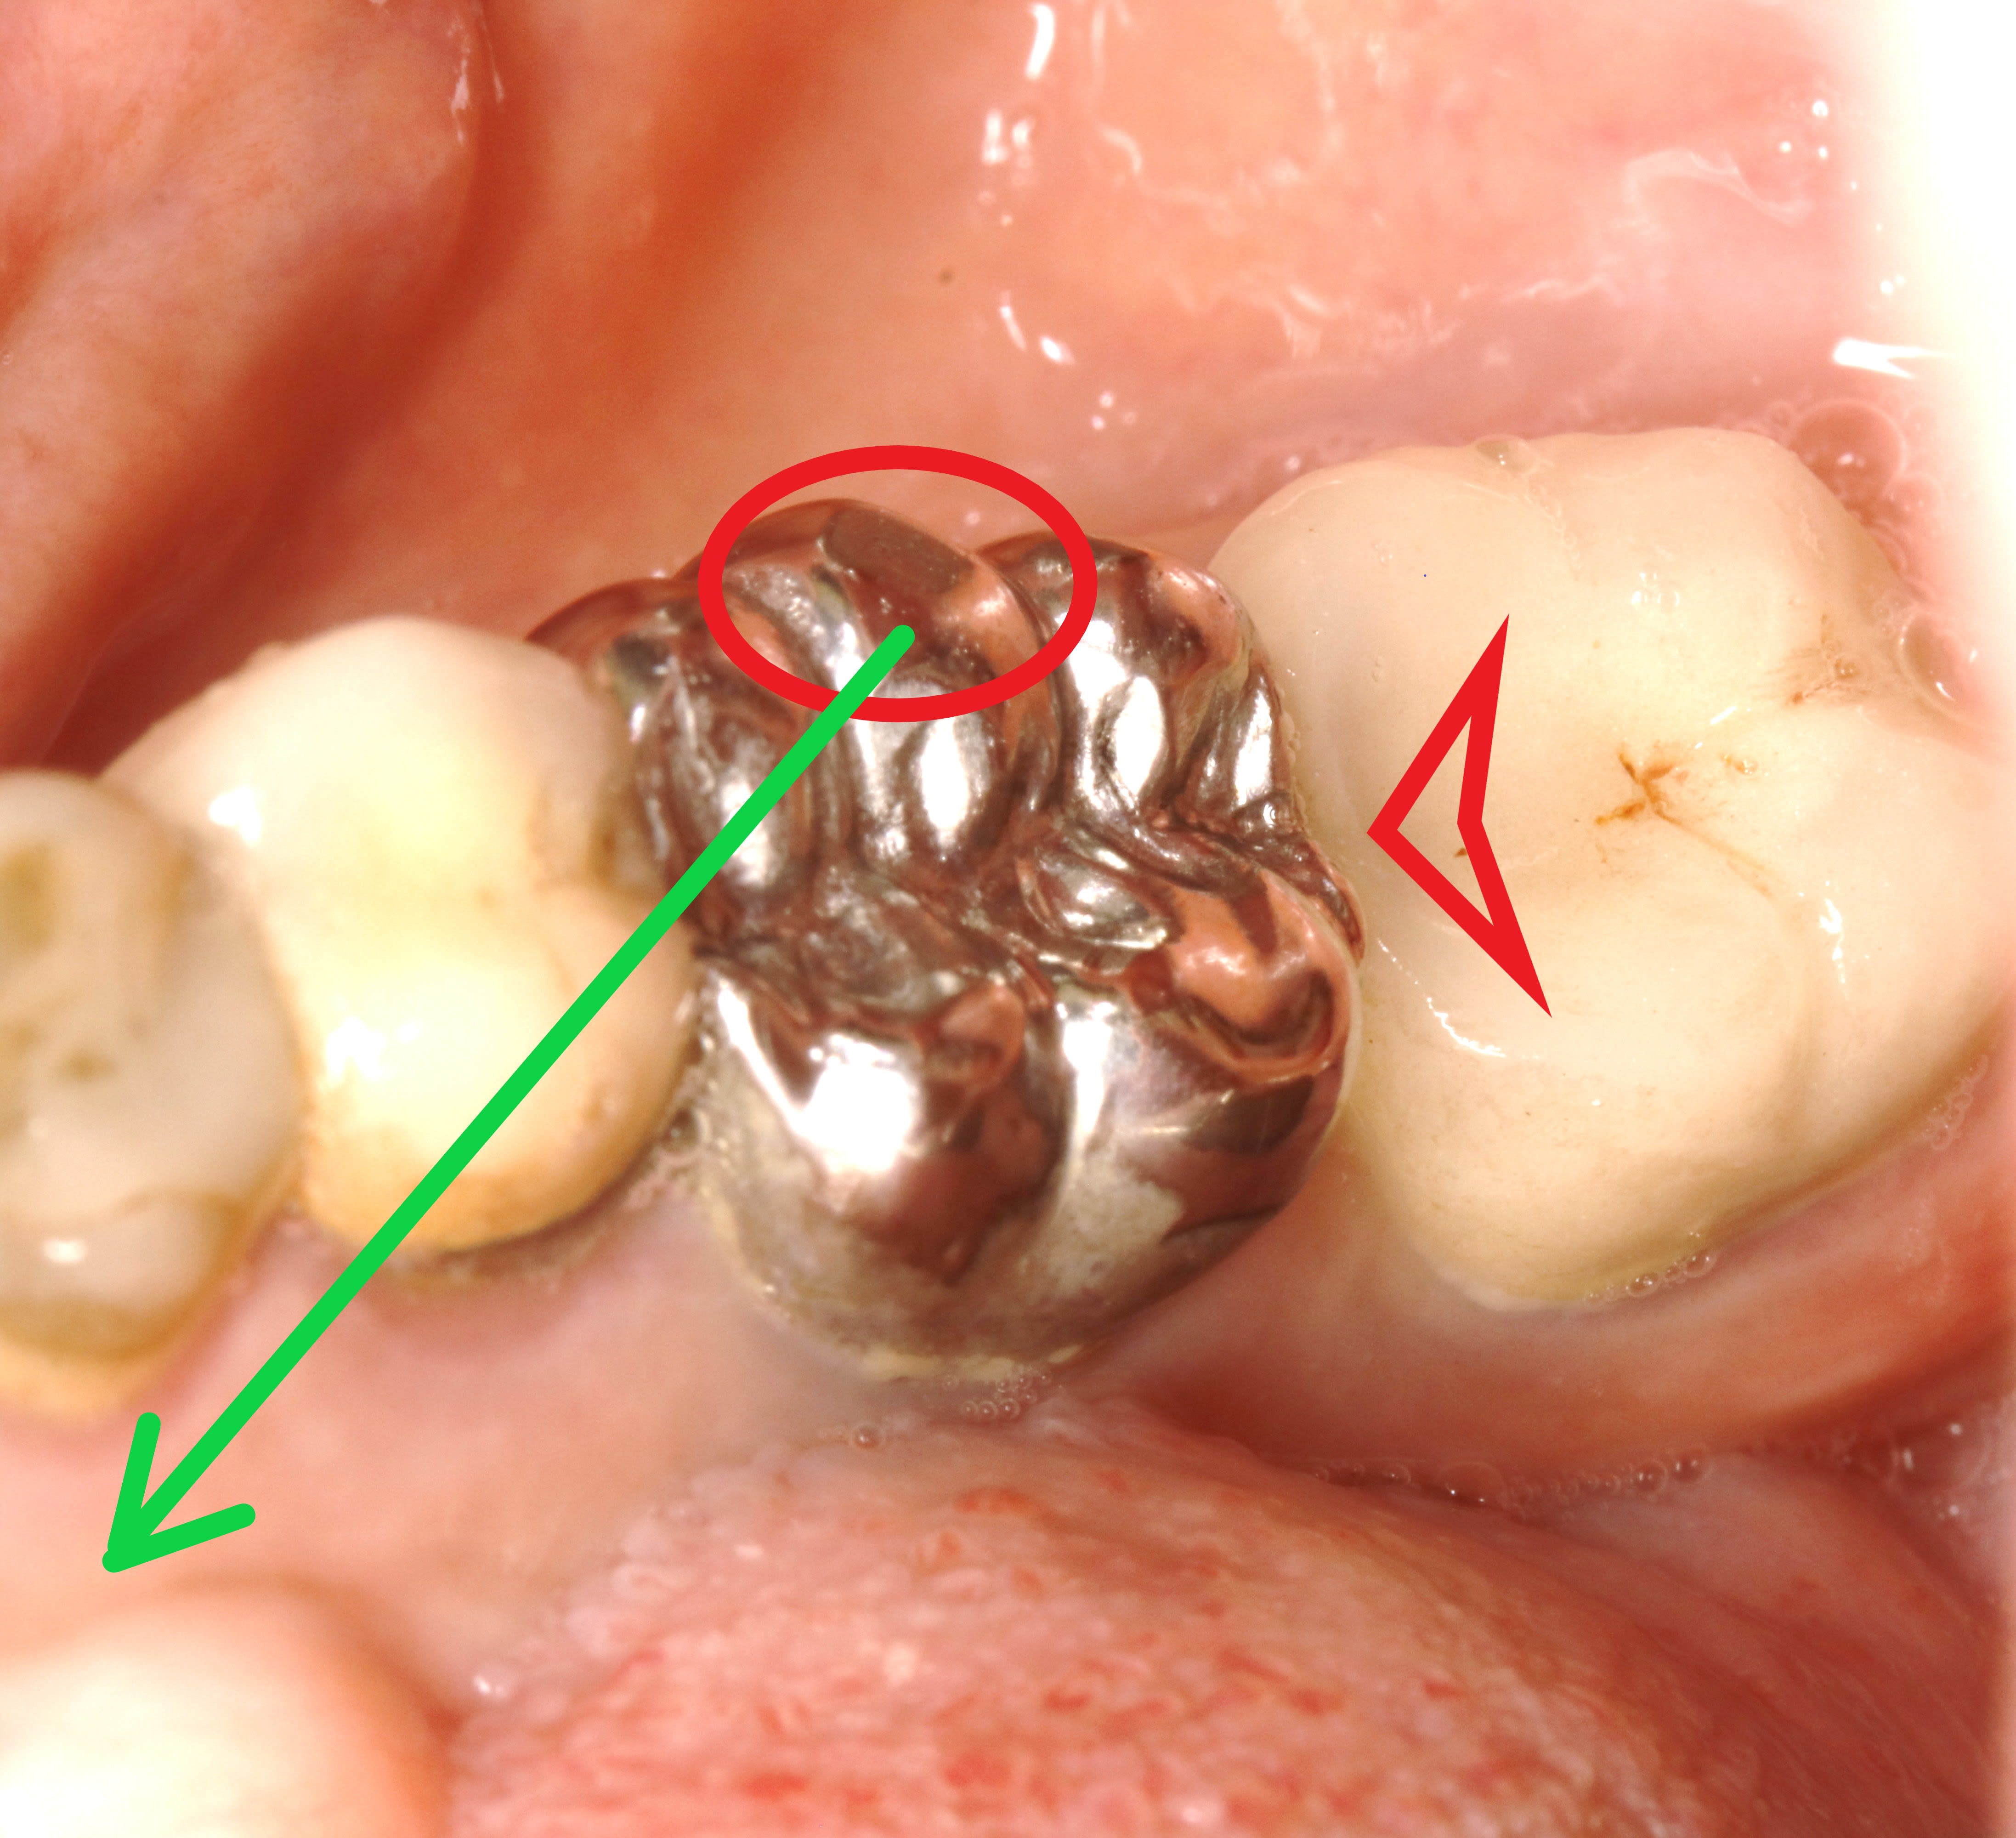

et qu est ce qu on voit ? une belle crete distale de la couronne metal qui forme une marche d escalier .

de toute évidence , ça s appelle une interférence en rétropropulsion .

or ç est une cl2 , donc sans guidage incisif efficient avant arriere .

ce qui veut dire que leurs chemins d entréé et de sortie sont amples , normalement .

et là , plus , blocage .

donc leur seul mouvement av / ar ne peut se faire qu avec un soubresaut .

Ce serait pas la crête mésiale de la 7 qui serait trop basse?-)) J'aime bien la morphologie occlusale de la 6 :-))

pcq comme l a dit Vulpi , ç est surtout la 7 qui ne va pas .

bien sur . en fait ce qui a du se passer ç est que la 6 , la plus ancienne n etait pas top avec de trop gros bombés y compris proximaux ,

du coup elle a du gangasser pour la mettre en place et elle a du user la reconstruction de la 47 donc celle d en haut a égressé .

puis récemment elle vient de faire faire la 47 mais son dentiste ne lui a pas corrigé celle d en haut avant .

un grand classique .

au final il faut quand meme enlever l escalier dans l urgence ,, avant de refaire 46,47 + l antagoniste de 47 .